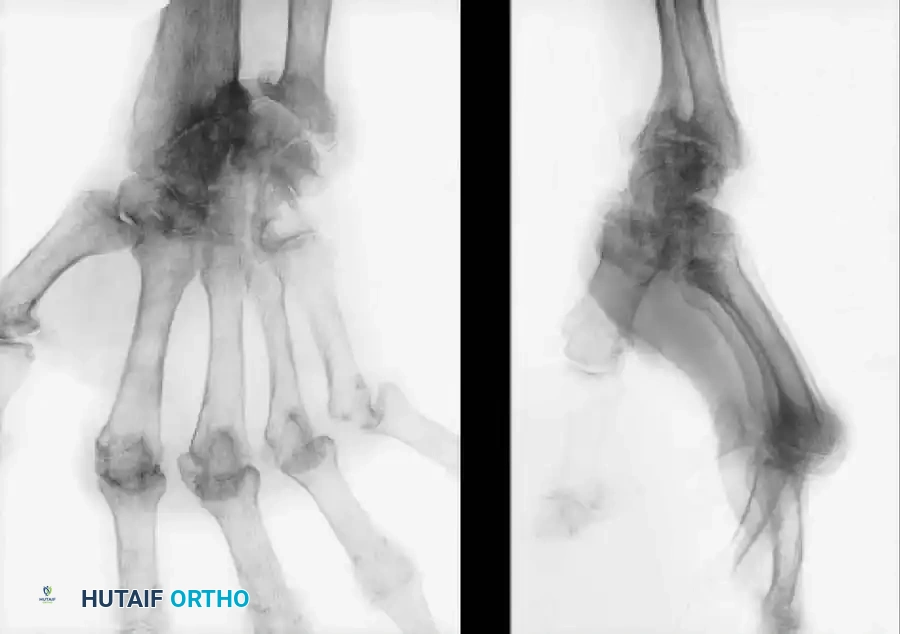

Biomechanically, the rheumatoid wrist undergoes a predictable pattern of collapse. The destruction of the radiocarpal ligaments—particularly the radioscaphocapitate and radiolunate ligaments—leads to ulnar translation and palmar subluxation of the carpus. Concurrently, the distal radioulnar joint (DRUJ) is compromised. Destruction of the triangular fibrocartilage complex (TFCC) and the stabilizing ligaments of the distal ulna results in dorsal subluxation of the ulnar head (Caput Ulnae Syndrome).

As the carpus translates ulnarly and subluxates volarly, the metacarpals angulate radially, which in turn contributes to the classic ulnar deviation of the digits at the metacarpophalangeal (MCP) joints. Furthermore, the extensor carpi ulnaris (ECU) tendon sheath is often destroyed, allowing the ECU to subluxate volarly. Once volar to the axis of rotation, the ECU ceases to act as a wrist extensor and becomes a deforming flexor force, exacerbating the palmar flexion and radial deviation of the wrist.

Clinical Presentation and Radiographic Evaluation

Radiographic evaluation is critical for staging the disease and planning surgical intervention.

* Early signs: Periarticular osteopenia, soft tissue swelling, and a characteristic "small pit" or erosion at the base of the ulnar styloid.

* Intermediate signs: Joint space narrowing, marginal erosions (particularly at the scaphoid waist and ulnar head), and early ulnar translation of the carpus.

* Advanced signs: Severe carpal collapse, complete loss of joint space, volar subluxation of the carpus off the radius, and severe DRUJ destruction.